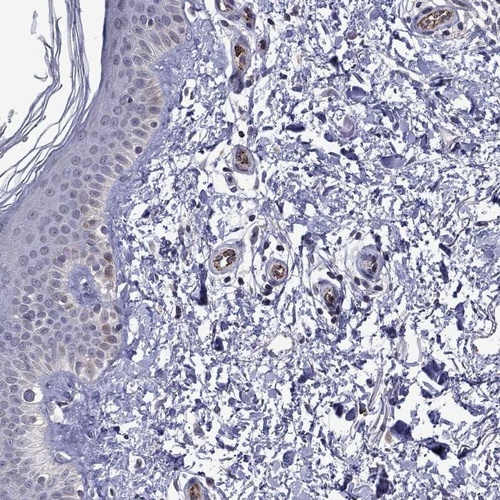

Immunohistochemistry analysis in human cerebral cortex and skin tissues using Anti-SLITRK1 antibody. Corresponding SLITRK1 RNA-seq data are presented for the same tissues.